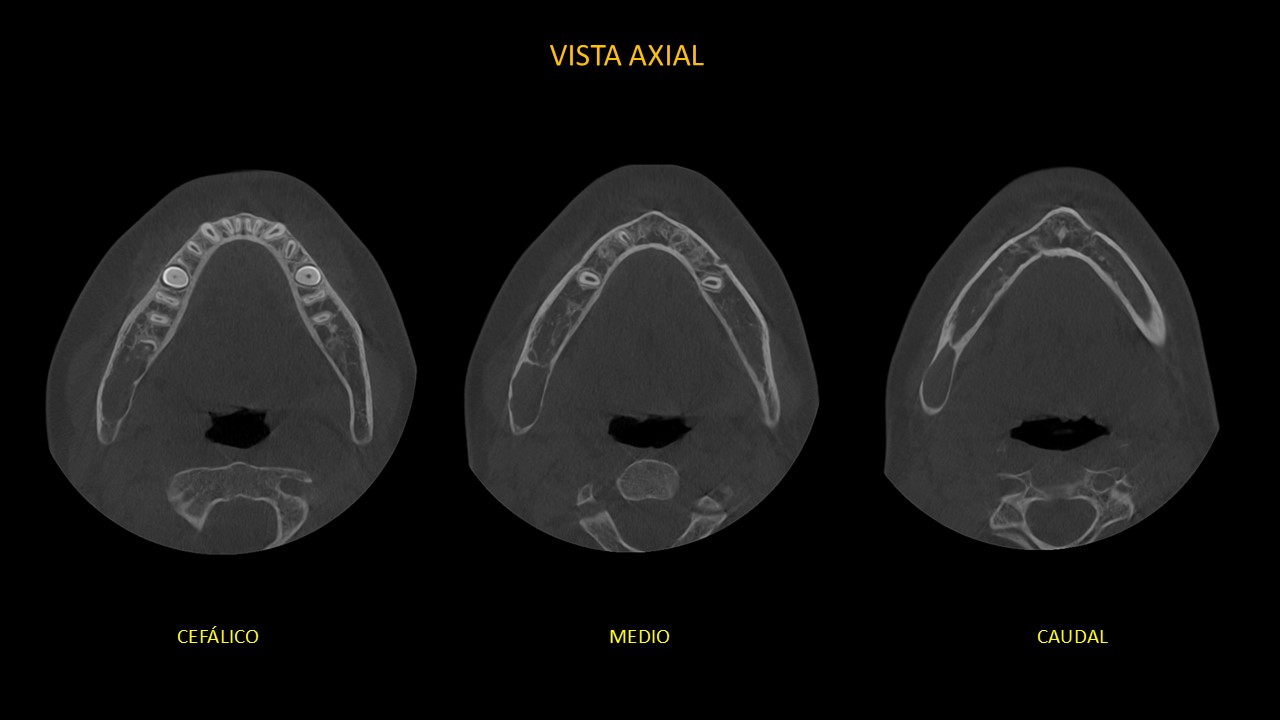

Figura 2

En cortes axiales (Figura 2), se observa el adelgazamiento de la tabla ósea vestibular y lingual; y leve expansión de la tabla ósea lingual.